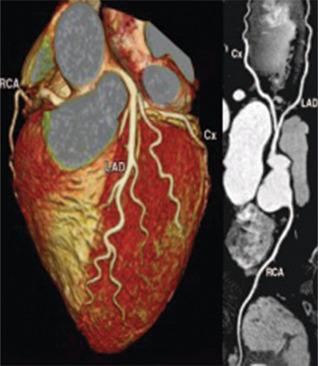

Cardiovascular diseases (CVDs) remain the leading cause of morbidity and mortality worldwide, and traditional preventive measures focus on lifestyle modifications, pharmacologic interventions, and risk stratification. Recently, imaging has emerged as an interesting tool in cardiovascular prevention. This review explores the role of various imaging modalities in early detection, risk assessment, and disease monitoring. Noninvasive techniques such as carotid ultrasound, arterial stiffness assessment, echocardiography, and coronary artery calcium scoring enable the identification of subclinical atherosclerosis and ventricular dysfunction, providing insights that complement conventional risk factors. Coronary computed tomography angiography and cardiac magnetic resonance offer high-resolution visualization of vascular and myocardial pathology, contributing to refined risk stratification. Furthermore, emerging markers such as epicardial adipose tissue and hepatic steatosis are gaining recognition as potential predictors of cardiovascular risk. Advancements in artificial intelligence (AI) are revolutionizing cardiovascular imaging by enhancing image interpretation, automating risk prediction, and facilitating personalized medicine. Future research should focus on optimizing the integration of imaging into clinical workflows, improving risk prediction models, and exploring AI-driven innovations. By exploiting imaging technologies, clinicians could enhance primary and secondary prevention strategies, ultimately reducing the global burden of CVDs.

心血管疾病(CVDs)仍然是全球发病和死亡的主要原因,传统的预防措施集中在生活方式改变、药物干预和风险分层上。最近,影像学已成为心血管预防领域一项引人关注的工具。本综述探讨了各种影像学检查方法在早期检测、风险评估和疾病监测中的作用。诸如颈动脉超声、动脉僵硬度评估、超声心动图和冠状动脉钙化积分等非侵入性技术能够识别亚临床动脉粥样硬化和心室功能障碍,提供补充传统危险因素的见解。冠状动脉计算机断层扫描血管造影和心脏磁共振成像能够对血管和心肌病变进行高分辨率可视化,有助于更精确的风险分层。此外,诸如心外膜脂肪组织和肝脂肪变性等新兴标志物正逐渐被认可为心血管风险的潜在预测指标。人工智能(AI)的进步正在通过增强图像解读、自动化风险预测和推动个性化医疗来彻底改变心血管成像。未来的研究应聚焦于优化影像学在临床工作流程中的整合、改进风险预测模型以及探索人工智能驱动的创新。通过利用成像技术,临床医生可以加强一级和二级预防策略,最终减轻全球心血管疾病负担。